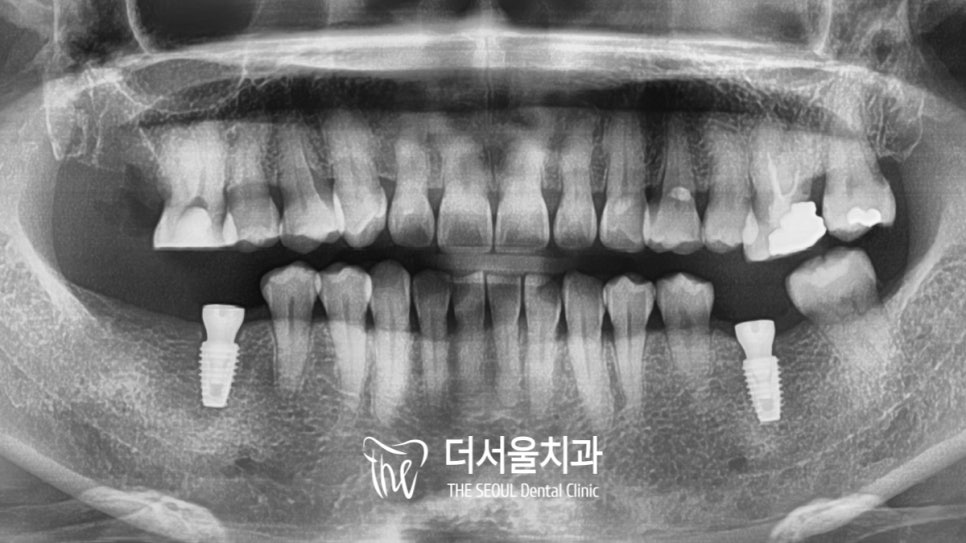

다행히 계획했던 곳에 올곧게 자리를 잡고 있는

성남 임플란트 를 확인할 수 있네요.

몇달의 시간이 흐르고

크라운을 올릴 날이 밝아왔습니다.

걱정과는 달리 자리를 잡고 있는

보철의 모습을 확인할 수 있었는데요.

충치치료를 했던 곳도 그렇고

예쁜 크라운이 올려져 있는 것을 확인할 수 있네요^^

다행히 6년이 지나도 처음 모습 그대로

관리가 잘 되어 있는 것을 확인할 수 있었죠.